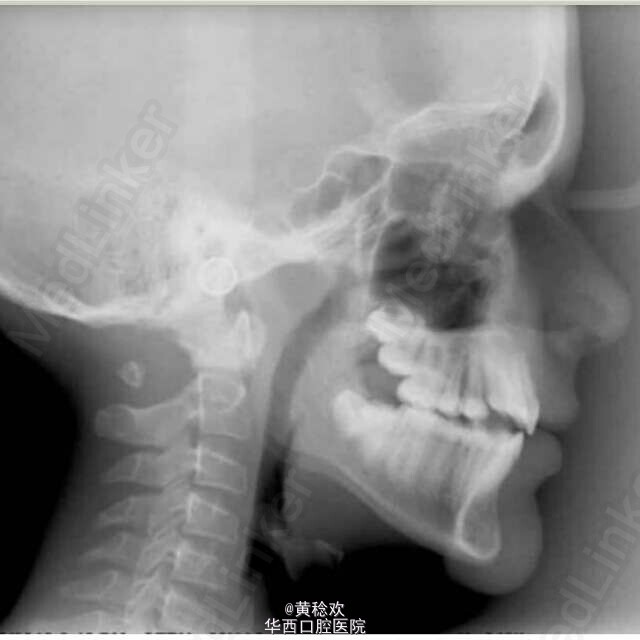

你能看出这张常规正畸头侧位片中的玄机吗?

13岁的男孩儿来正畸科求治,面部对称,全身健康状况可,拍摄常规头侧位X片时却发现了一个潜在的严重问题,你能看出这是什么吗? 图片来源: figure 1 . app